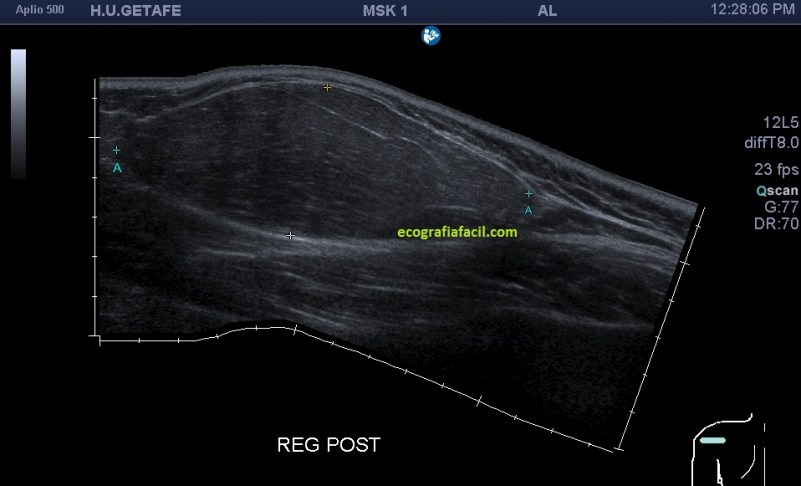

Uno de estos problemas lo vemos en este Caso 2 que te planteo a continuación y puede ser el volumen de la lesión…cuando nosotros tenemos una lesión de gran tamaño, acotarlo para poder medirlo es complicado, en ocasiones necesitaremos «Panoramic View». Te presento este caso distinto del anterior, de un gran lipoma, de más de 10 centímetros que es inmedible si lo hacemos con la huella del transductor lineal que no supera los cinco centímetros. Al poner el transductor nos encontremos esto:

La imagen 9 en la cara posterior del hombro de una lesión que ya aparece enorme, hipoecogénica y homogénea, pero cortada por ambos lados porque con la sonda de alta frecuencia no nos da…¿qué tenemos que hacer?, usamos panoramic view si disponemos de esta función para tener esta imagen:

Cuando hacemos un recorrido sobre la lesión descubrimos que tiene casi 11 centímetros de eje largo. Al contrario de la imagen del caso anterior, vemos una imagen enorme, hipoecogénica o isoecogénica junto con la grasa del tejido celular subcutáneo, que puedes ver en este detalle anatomoecográfico: